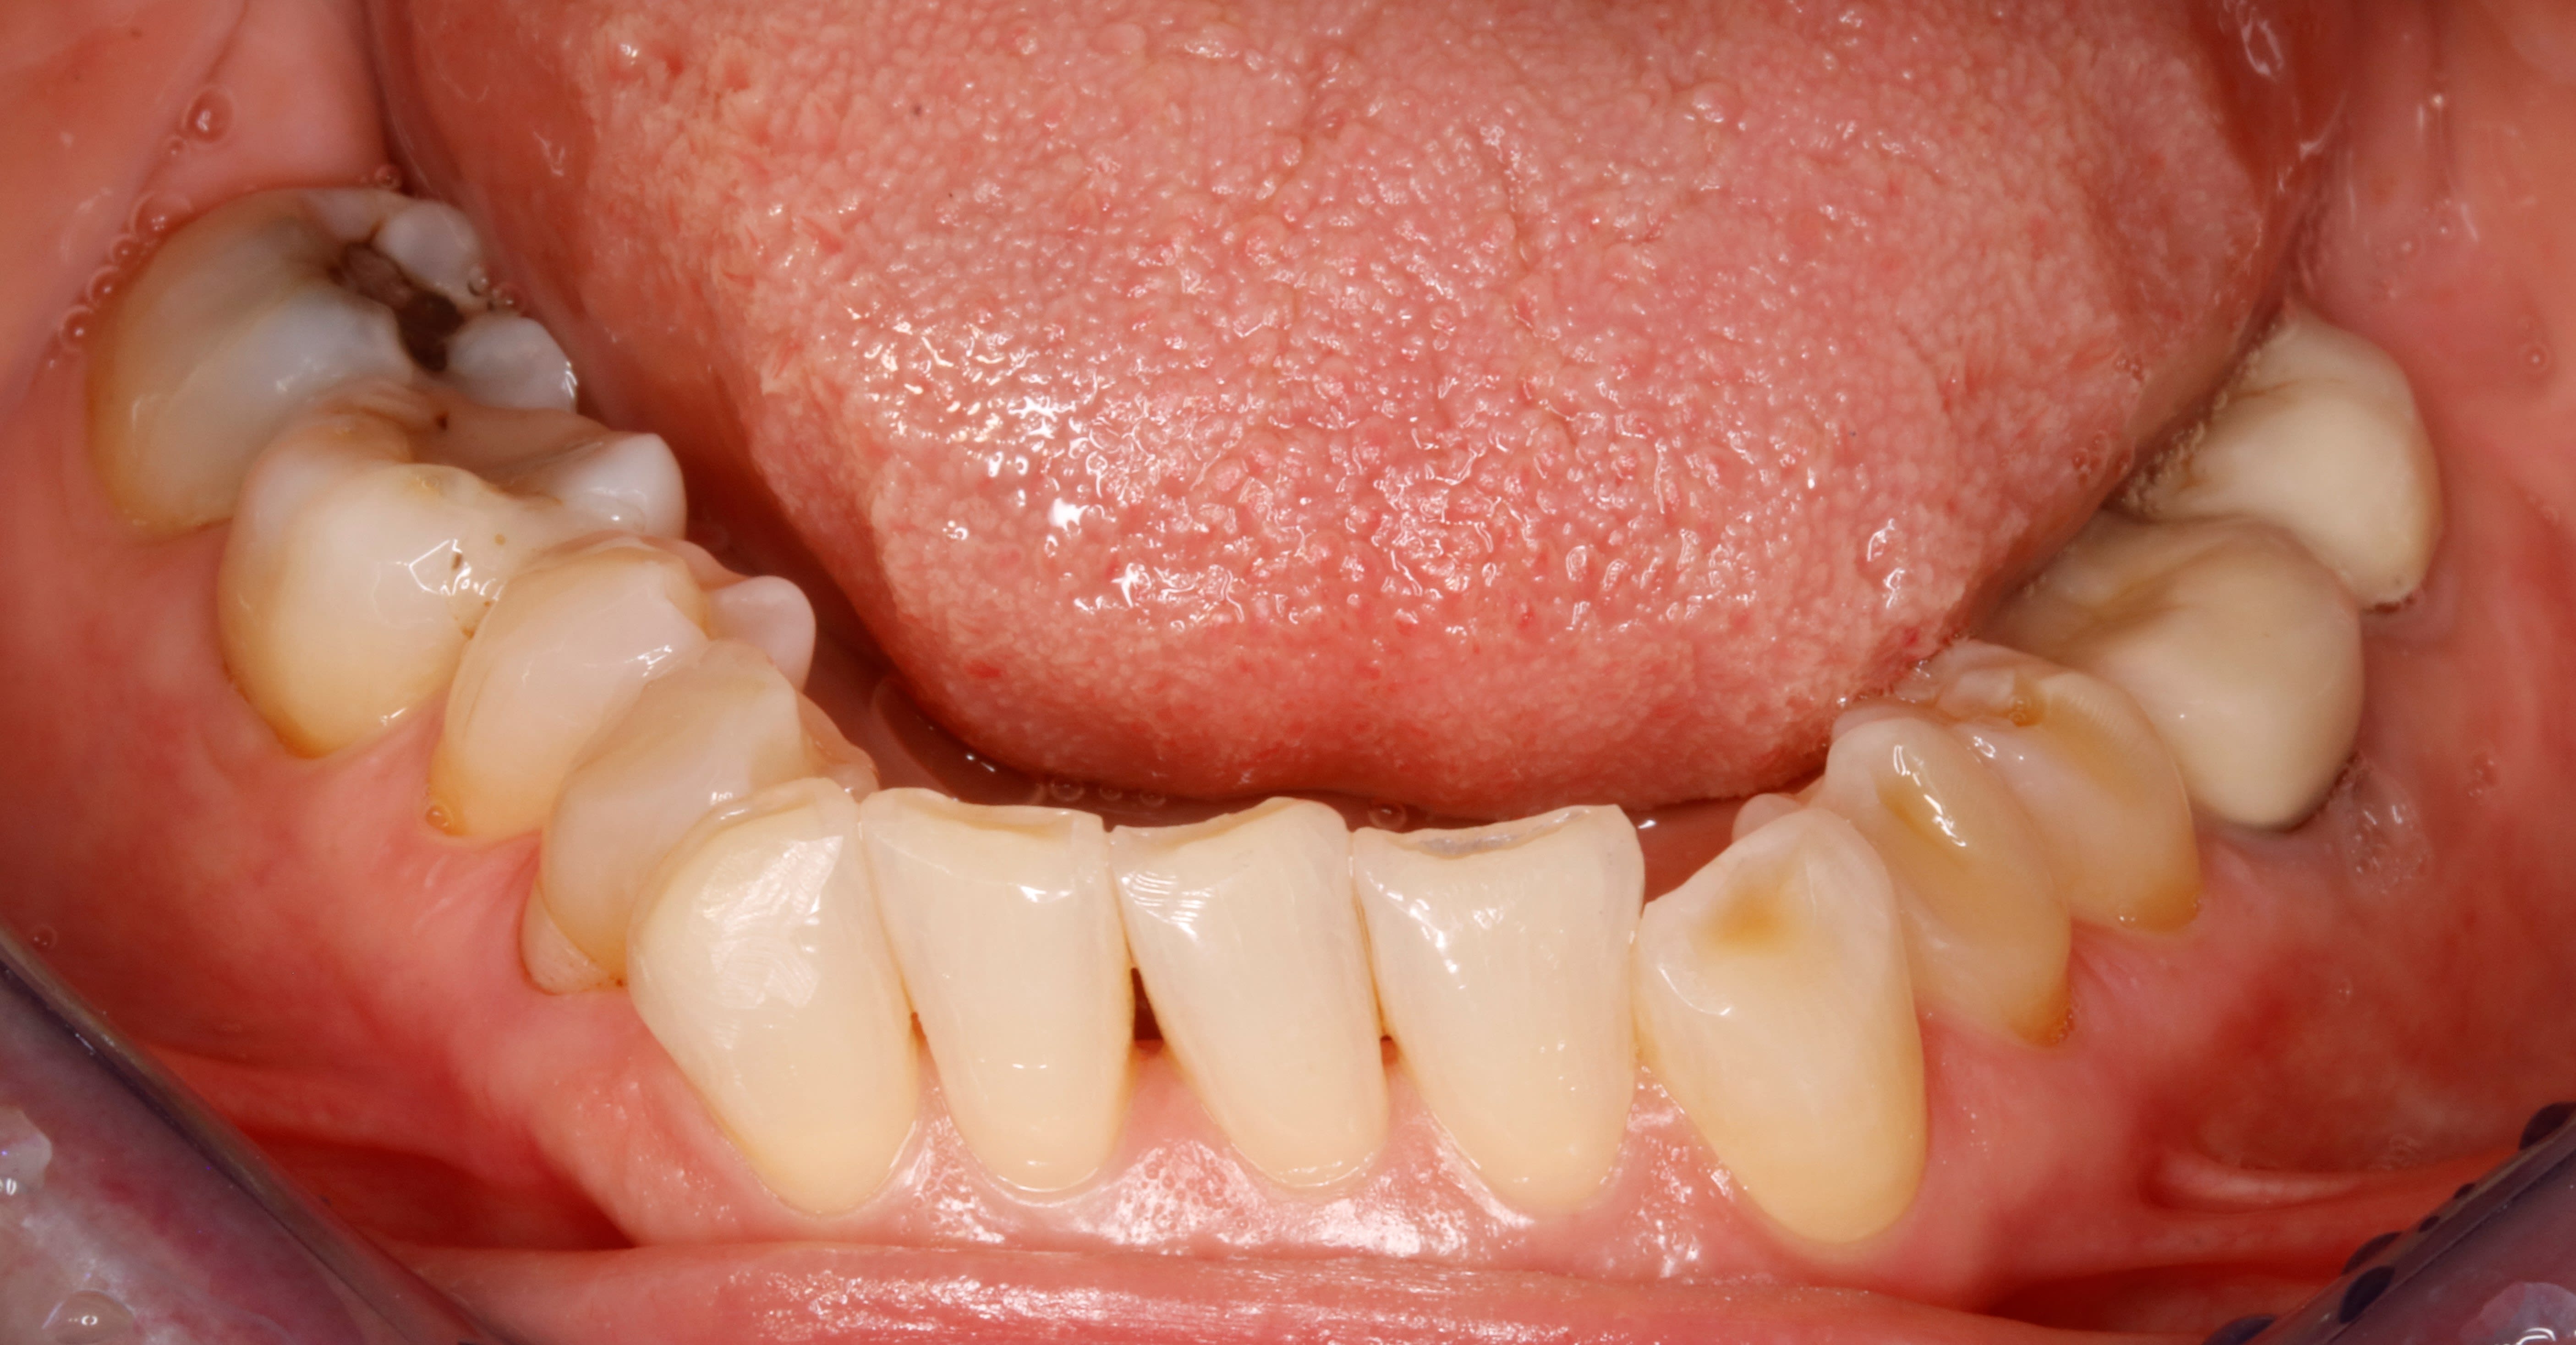

Elle penche à droite car il manque la 42

Les prémo inf sont trop lingualées,

j y vois une supraclusion , de l usure , un passif orthodontique par l absence de PM , une asymétrie des incisives du bas , un sur guidage ant , bref que cette occlusion d aujourd'hui , n est certainement pas celle d'hier et qu il y a bien eu une dérive latérale .

Pour moi le problème de la 12 vient aussi de l absence d une incisive mandibulaire. Cela induit une distance inter canine plus petite. Donc la pointe canine se retrouve mesialée par rapport à sa position idéale. Donc elle use a bloc les angle D de son bord libre des incisives latérales maxillaires. Pas de bol c est moche. Su coup elle veut des dents plus longues / plus belles/ mais sans tenir compte de son schéma global de mastication. Du coup ça pète.